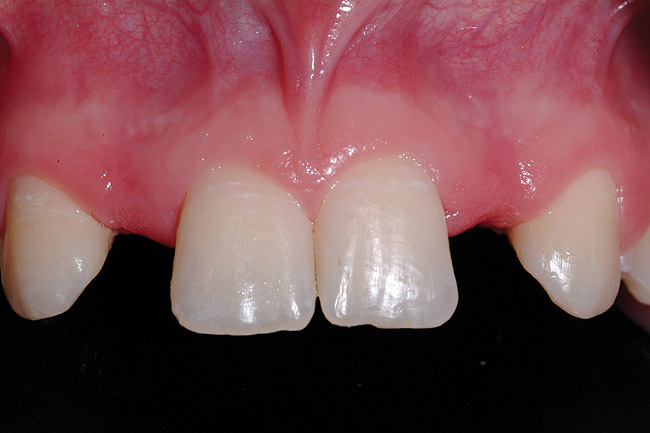

Figure 4  Pretreatment clinical view, right lateral incisor.

Figure 4

A 19-year-old non-smoking female presented for tooth replacement at the maxillary right and left lateral incisors, which were congenitally missing (Figure 1). The post-orthodontic result was adequate for the placement of 3-mm one-piece small-diameter implants. The preoperative radiographs can be seen in Figure 2 and Figure 3. The pretreatment clinical view in Figure 4 and Figure 5 shows the small intertooth space present in the lateral incisor areas. One of the most challenging tasks with congenitally missing lateral incisor cases is to create an acceptable soft tissue emergence profile from a crestal profile that is flat from the mesial of the canines to the distal of the centrals (Figure 4 and Figure 5). After pretreatment planning which consisted of a complete medical and dental history, radiographic analysis, and upper and lower study models mounted by a facebow transfer technique, the fabrication of a TempStent II surgical guide was completed. Figure 6 and Figure 7 show the occlusal view of the TempStent II guide on the study cast and in the oral cavity, respectively.